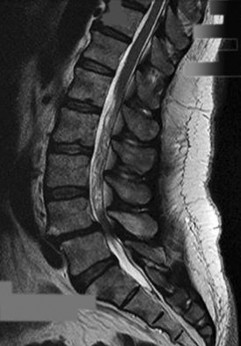

On a sagittal MRI of the lumbar spine, a vertebral body endplate adjacent to a degenerated disc shows hypointense signal on T1-weighted images and hyperintense signal on T2-weighted images. This finding corresponds to which Modic type, and what does it pathologically represent?